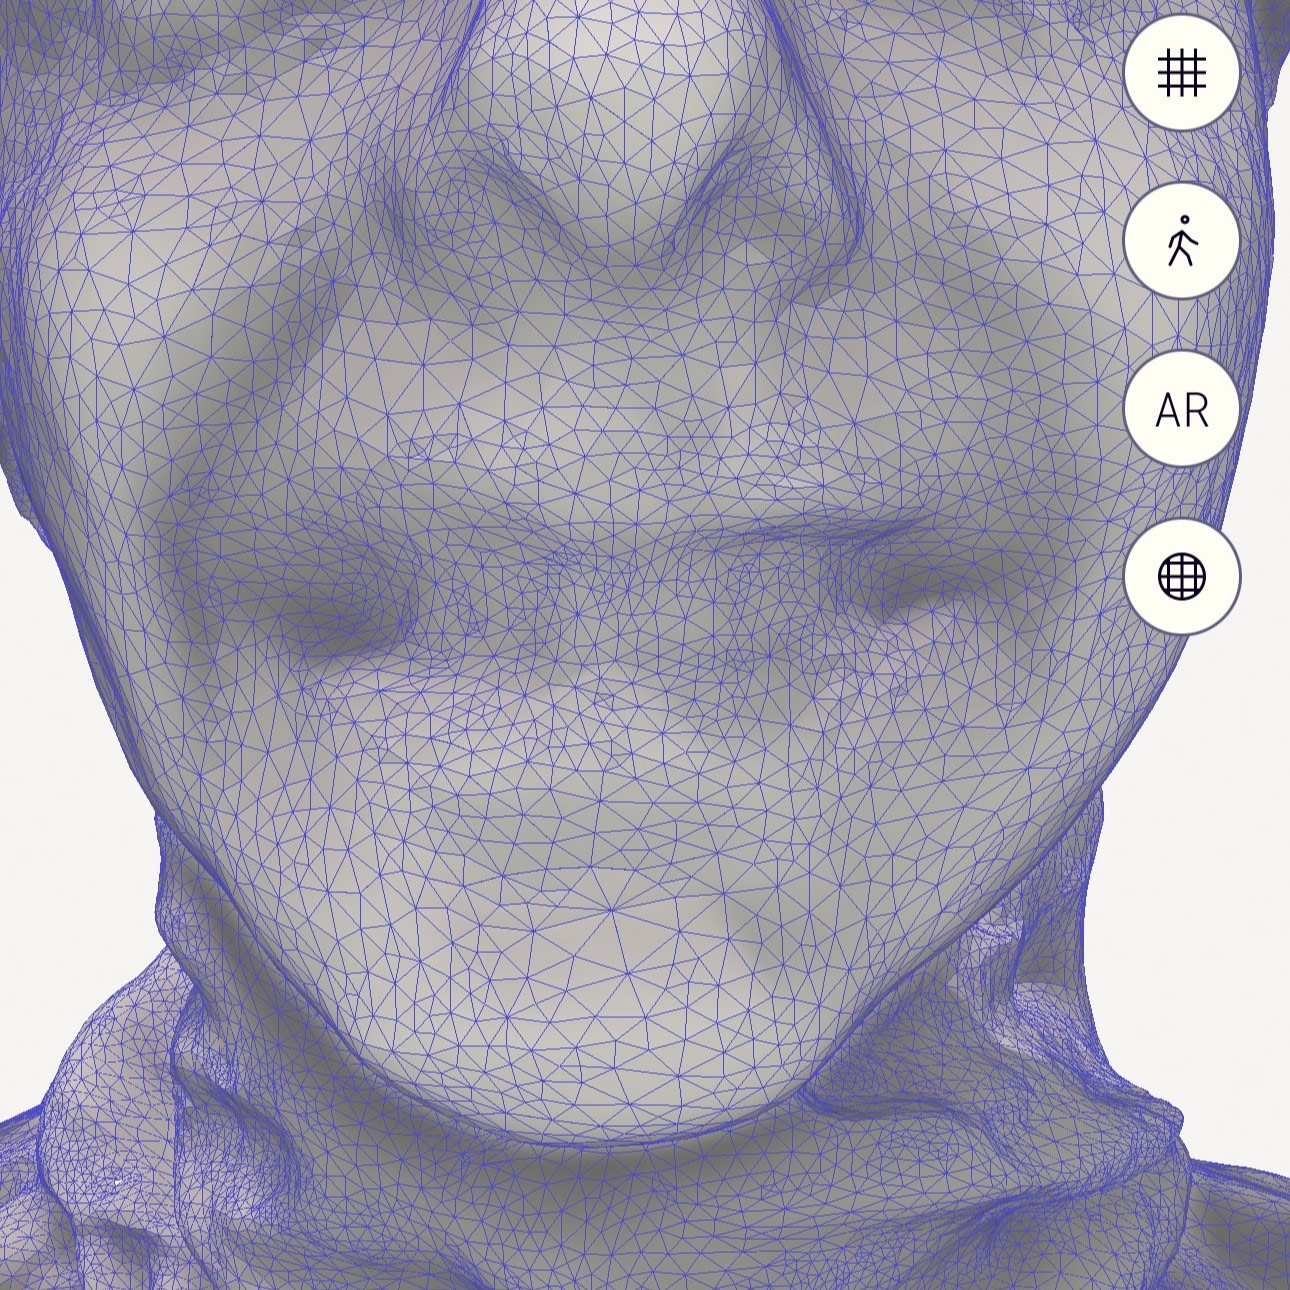

Also note the distortion in the face scanning with iPhone apps. It is interesting to see how the edges of the teeth are not exactly perfect. How much does this impact the alignment of IOS? Let's check without colour.

The iPhone apps don't do as well and don't seem to have the resolution. With the original Qlone app you can see the downfall of this and many iPhone apps that are used to take a face scan. Although they can make the colour image look good, when you turn off the colour, you can clearly see the issues. How do you align an intraoral scan to this confidently?

In saying that, the new Qlone Dental Pro is a big improvement no doubt. So these are not just marketing claims. The new app really does capture the teeth and lips to a higher detail - but this cannot be thanks to hardware as I am using the same phone - it must be just smarter algorithms.

Although with the new app there is much more detail to be seen, the question is - does this look like the patient's actual teeth?

Aligning the IOS data to the face scan data is simple - by choosing multiple points of reference on both data sets. You are trying to find the same points on both the IOS and face scan, so the clearer the face scan, the easier and more accurate this is.

Therefore, the better the details of the teeth on the face scan, the more likely it is going to be an accurate alignment. And if you're going to rely on this for your cosmetic wax up etc, you want this as accurate as possible.